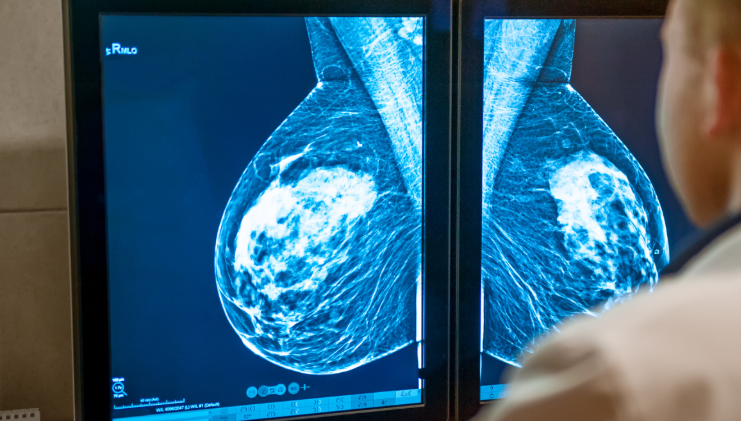

유방촬영(맘모그래피)에서는 유선 조직이 많을수록 하얗게 보입니다. 문제는 혹이나 종양도 같은 흰색으로 나타난다는 점입니다. 이 때문에 치밀유방에서는 이상 병변이 가려질 가능성이 있어 영상의학과에서는 이를 별도로 표시합니다. 하지만 이 결과만으로 질병을 판단하지는 않으며, 정확한 평가는 초음파나 다른 검진 결과와 함께 종합적으로 이뤄집니다.

검진에서 치밀유방이 중요한 이유는 ‘조기 발견의 어려움’ 때문입니다. 유선이 빽빽하게 차 있으면 혹이 숨어 있을 가능성이 있어 맘모그래피만으로는 충분한 판독이 어려울 수 있습니다. 그래서 치밀유방으로 판정된 경우에는 초음파 검사를 함께 진행하기도 합니다.